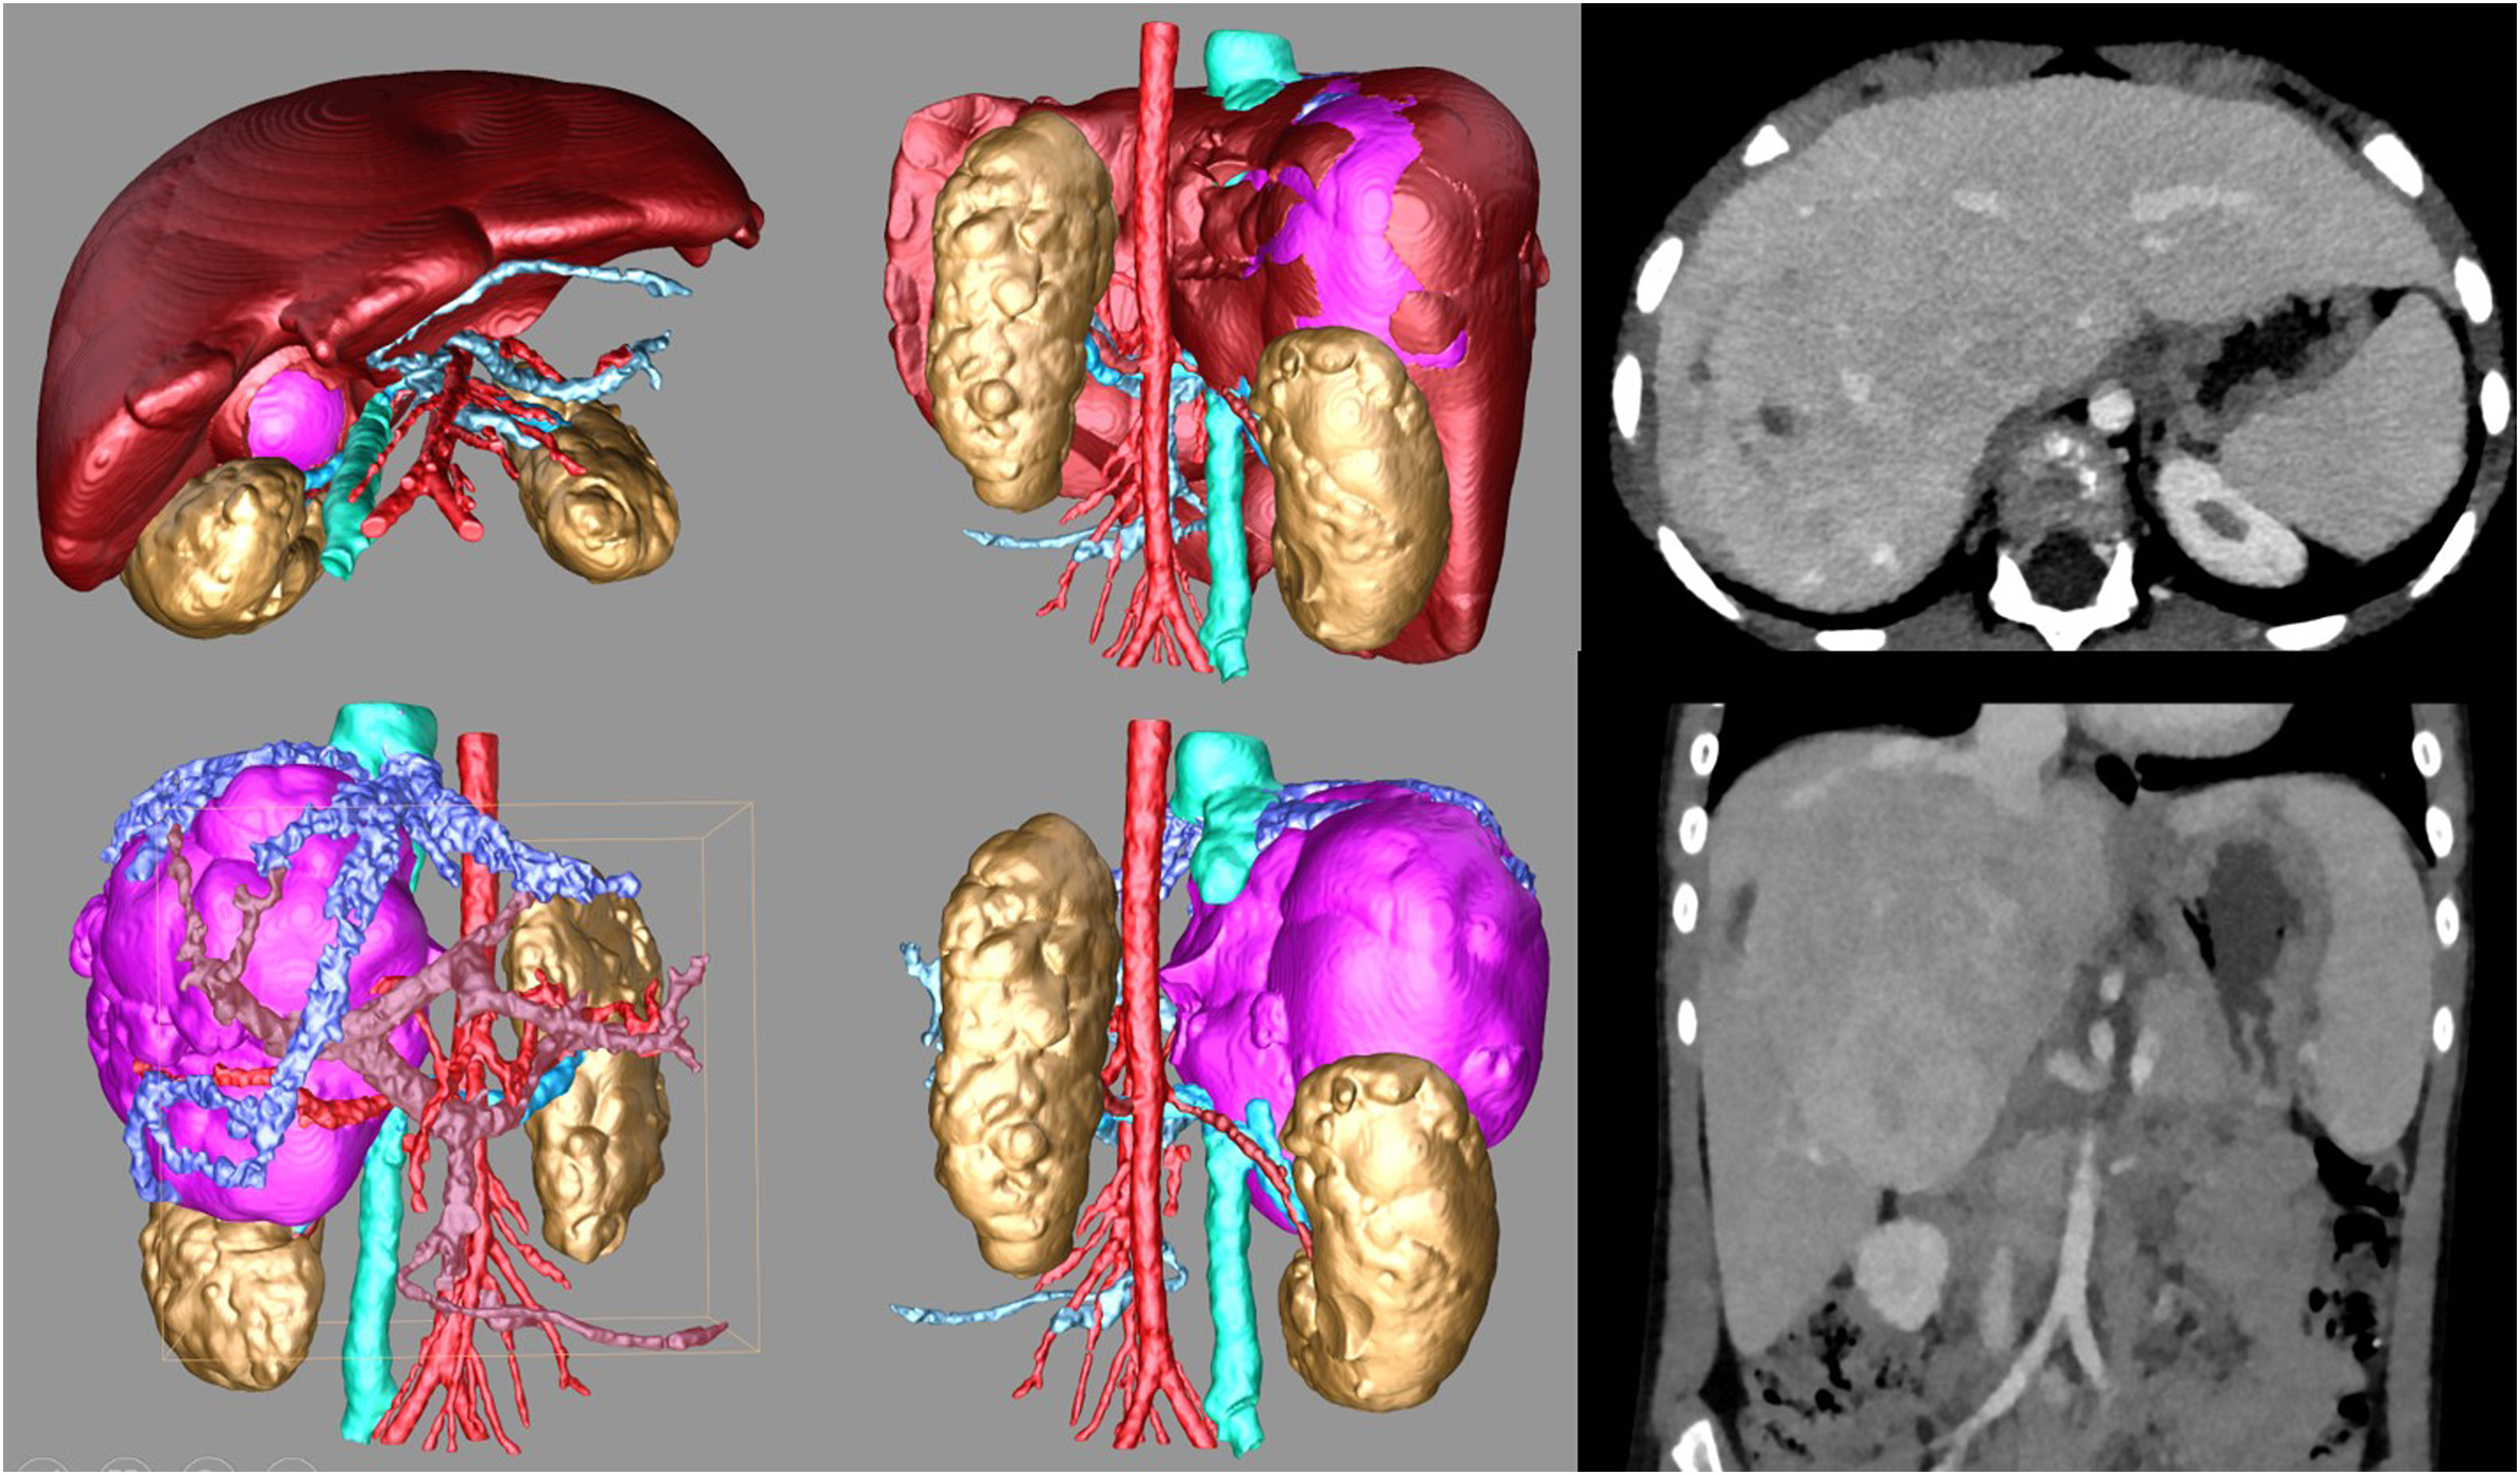

Advances in computed tomographyNovel computed tomography (CT) techniques include dual-energy and photon-counting systems with enhanced image quality and lower radiation doses. Dual-energy CT scanners can generate virtual unenhanced images that allow visualization of kidney stones or iodine maps that can be useful for visualization of lung perfusion in cases of pulmonary embolism. Photon-counting CT (PCCT) scanners generate higher-quality images with lower radiation and contrast doses. It is estimated that PCCT could reduce radiation doses by approximately 30%–60%, depending on the imaging protocol and clinical question.2 These advances allow mapping and quantification of iodine uptake, achieving more accurate tissue differentiation, enhanced material decomposition and improved three-dimensional reconstruction of tumors and 3D printing, facilitating planning of complex surgeries and integration of imaging and surgical robotics, and therefore contributing to advances in image-guided surgery (Fig. 1).